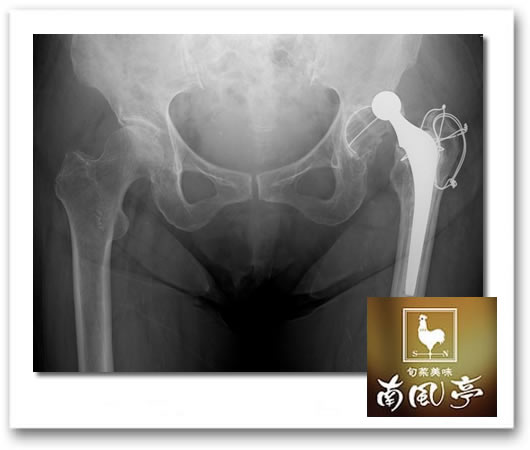

fumie 昨日夜のお客さま来店30分前に2度めの脱臼、2度めの救急搬送😱 局部麻酔で修復できたのでよかった❣ 半年の間に3回入院なんて私ってスゴイ❓ 2月の手術前に担当医から脱臼の怖さを聞かされ、「それも2回脱臼する人もいるんですよ」との言葉に「エーッ!そんな人いるんですかー?」って私。 やっちまった!その2回めだ私。もう3回めがないようにスローな動作を心がけることを誓います。

葉羽 ええ~!(※画像はイメージ。別人のもの。)